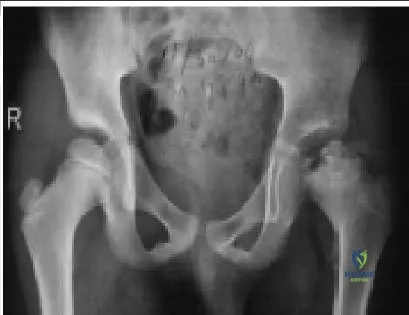

Which of the following disease processes is demonstrated in the radiograph (Slide):

The left femoral epiphysis shows avascular changes characteristic of Legg-C alve-Perthes disease without slippage. Although developmental dysplasia of the hip may also be complicated by avascular changes, the femoral neck and acetabulum would manifest more longstanding growth alterations as well. The contralateral hip would be symmetric in patients with multiple epiphyseal dysplasia.